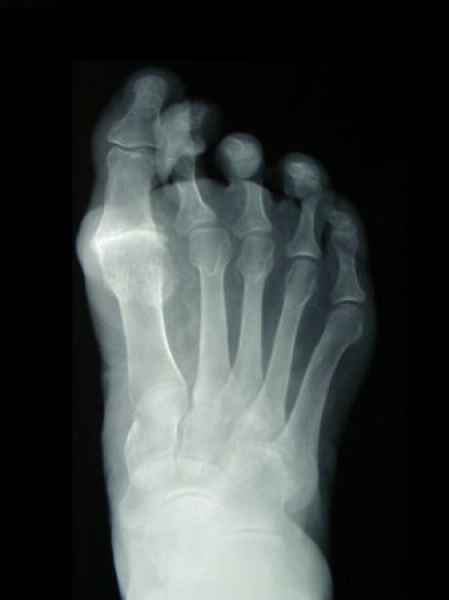

El pie es el órgano distintivo y característico de la especie humana, la única criatura que marcha erguida. El pie es una muy compleja estructura de arquitectura perfecta, adaptado a su función de apoyo, traslación, salto, con una riquísima sensibilidad que le permite detectar las más leves imperfecciones del suelo para estabilizar la marcha.

Tanto la estructura del pie como su funcionalismo que es la marcha, pueden ser asiento y manifestación respectivamente de alteraciones locales ó sistémicas, por lo que su cuidadoso examen resulta de extrema utilidad diagnóstica.